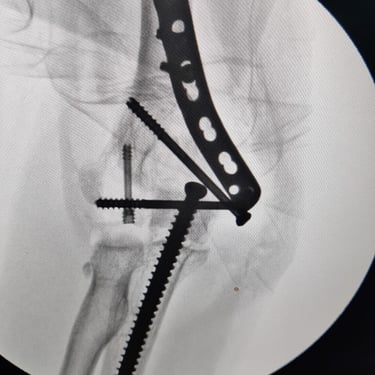

Limb reconstruction and complex trauma surgery

Trauma (Fractures)

Orthopedic trauma (fractures) refers to injuries to the musculoskeletal system, like bones, joints, and muscles, often from accidents, falls, or sports